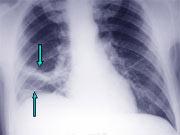

问题 该病人突发胸部疼痛,进行性呼吸困难,行X线片检查,提示右下肺病变,急诊CT平扫加增强,如图所示,则 ( )

选项 A.X线片示右下肺实变影 B.SCT增强扫描示右侧肺动脉主干完全性充盈缺损 C.右肺动脉开口处见不规则软组织密度影 D.考虑为右侧肺动脉(中央性)栓塞 E.考虑为右侧肺癌

答案 ABCD